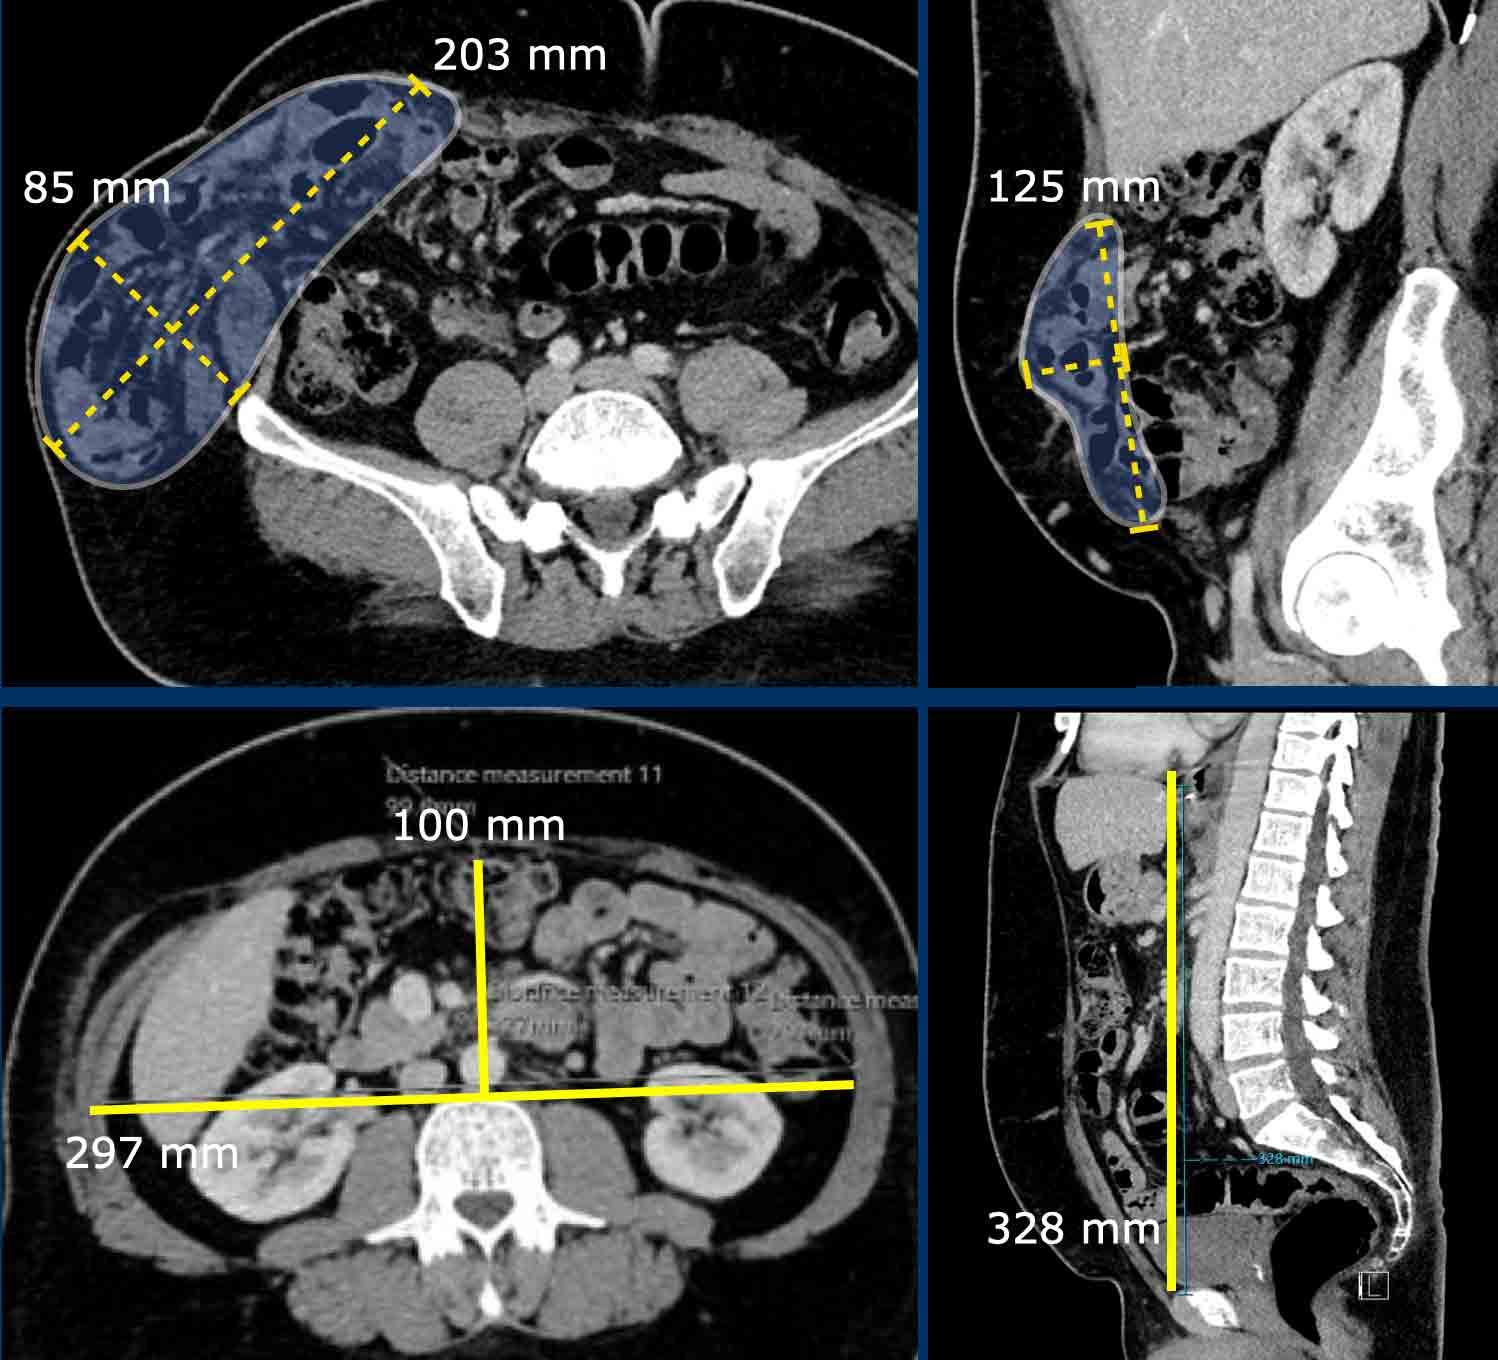

Đo kích thước trong trường hợp nhiều thoát vị

Bệnh nhân này có hai thoát vị.

Có một thoát vị đường giữa (đầu mũi tên màu vàng) và một thoát vị bên (đầu mũi tên màu trắng).

Trong trường hợp này, tổng chiều dài kết hợp và tổng chiều rộng được đo.